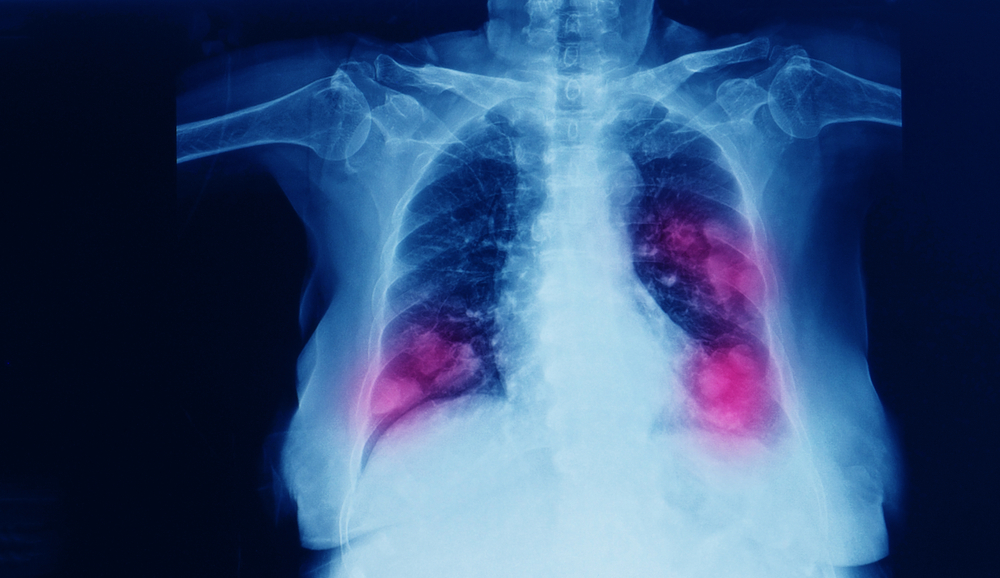

ជំងឺមហារីកអាចរាលដាលទៅស្ទើរគ្រប់កន្លែងនៃរាងកាយ ទោះបីជាជំងឺមហារីកប្រភេទខ្លះទំនងជារាលដាលទៅតែកន្លែងជាក់លាក់មួយចំនួន ជាជាងកន្លែងផ្សេងក៏ដោយ។ ផ្នែកនៃរាងកាយដែលមហារីកជាទូទៅច្រើនរាលដាលទៅមានដូចជាឆ្អឹង ថ្លើម និងសួត។

- មហារីកសួត៖ អាចរាលដាលទៅកាន់ ក្រពេញលើតម្រងនោម ឆ្អឹង ខួរក្បាល ថ្លើម និងសួត។

- ហត់ ពេលជំងឺមហារីកឆ្លងដល់សួត